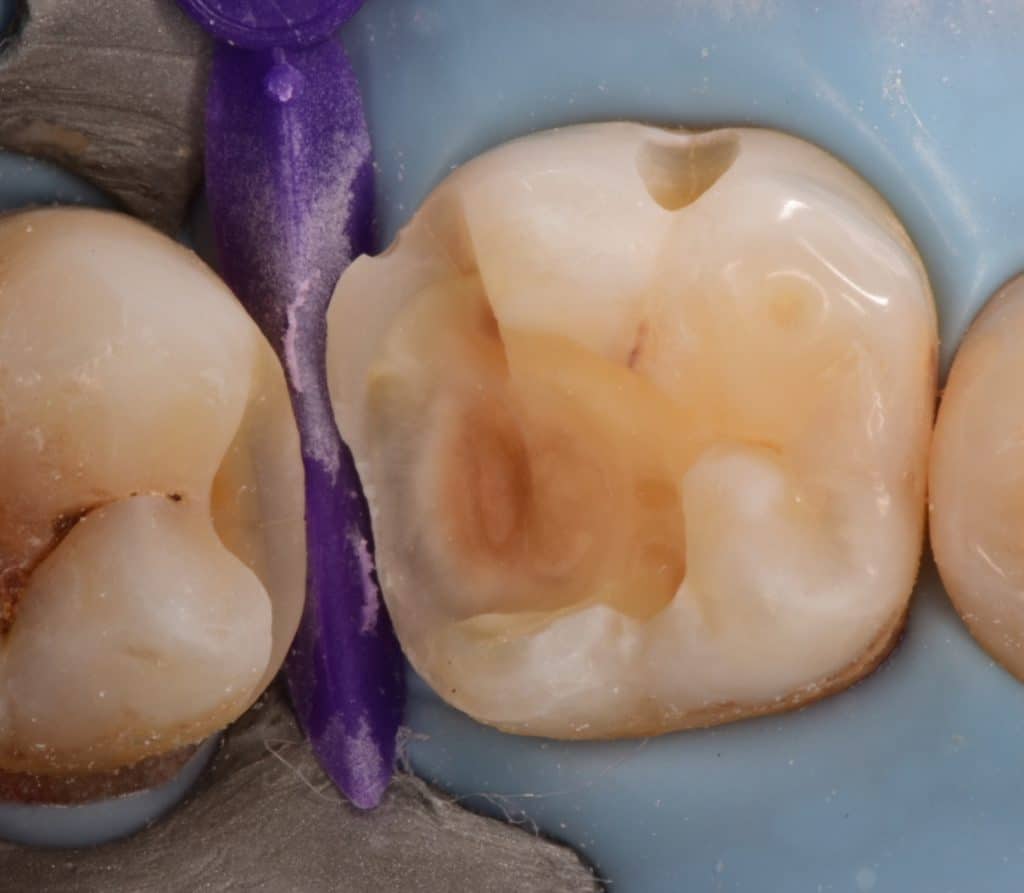

Mesail wall of the Lower second molar prepared and cleaned

Final cavity design after sandblast

Selective enamel etching

IDS with gold standard clearfil SE bond, RC with GC flowable composite, second molar restored first

Occlusal view